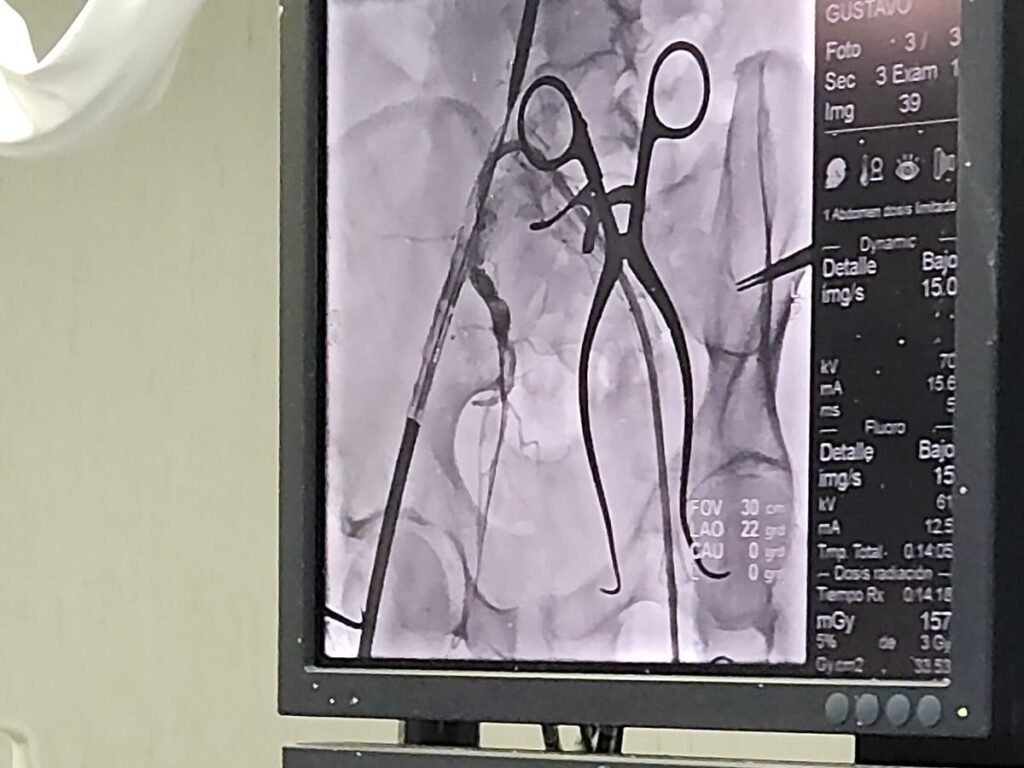

En un nuevo logro de la salud pública argentina, los equipos de Cardiocirugía y Hemodinamia del Hospital Presidente Perón de Avellaneda realizaron con éxito la reparación de un aneurisma de la aorta abdominal (AAA) de 84 mm mediante un procedimiento minimamente invasivo, evitando así la cirugía abierta tradicional.

La intervención consistió en canalizar la aorta a través de las arterias de las piernas y colocar un recubrimiento especializado, lo que permitió tratar la afección de manera segura y personalizada. El procedimiento, conocido como “T Branch”, es innovador en el país y se adapta a las necesidades específicas de cada paciente.

En este caso, la endoprótesis fue diseñada a medida, garantizando un abordaje individualizado y eficaz. Este tipo de intervenciones demuestra cómo la salud pública puede ofrecer tratamientos de alta complejidad y tecnología de vanguardia, asegurando atención de calidad sin necesidad de recurrir a la cirugía abierta.